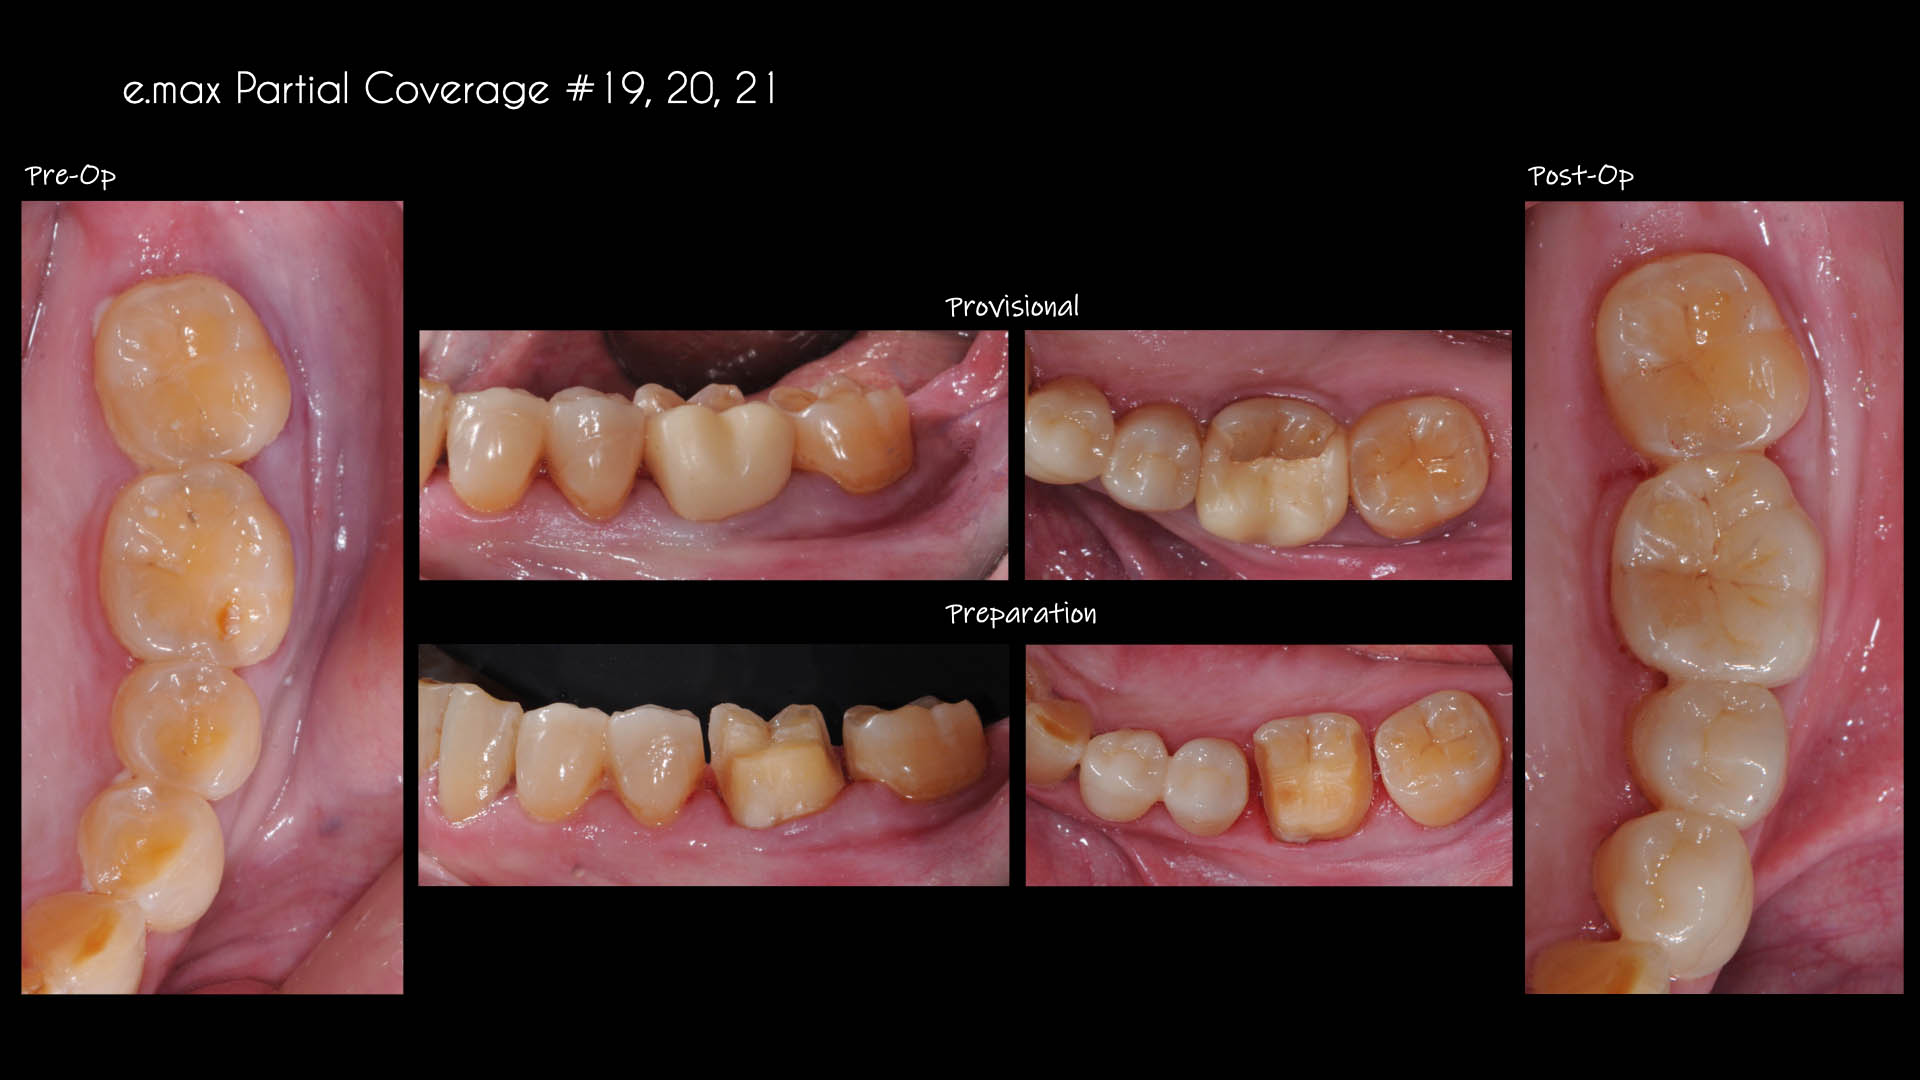

Take a glimpse into the magic of Coral Gables Dentistry through our before and after pictures. See firsthand the incredible smile makeover transformations that have brought confidence and joy to our patients.